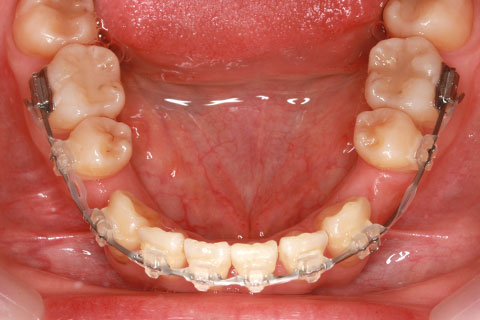

ハーフリンガル矯正3:上の歯のみ舌側矯正で治療(矯正期間24ヶ月)

治療前

治療中(開始直後)

治療中(開始半年後)

治療後

- 年齢・性別

- 25歳女性

- 治療期間

- 2年0ヶ月

- 抜歯

- 上下4番抜歯

- 治療費

- 110万円

- 治療内容

- 表側矯正と比較して、力学的な操作性が複雑なため、ボーイングエフェクトを起こしやすい。